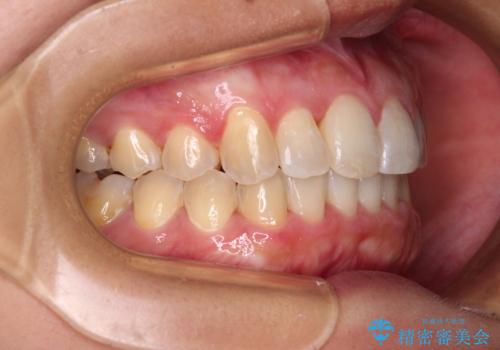

前歯のデコボコをインビザラインでスッキリと仕上げる

- 上下前歯のデコボコと奥歯の銀歯を気にして来院された患者様です。

口元をインビザラインにより歯列を整え、その後に失活している奥歯をオールセラミッククラウンにて補綴治療することとしました。

長時間のマウスピース装着に協力いただき、自然な口元に仕上げることができました。

気になっていた銀歯もオールセラミッククラウンで本物の歯のようになり、患者様には大変満足していただきました。